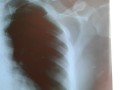

Taveras fue diagnosticado con fracturas en la clavícula y otras partes del cuerpo, al tiempo que denuncia se llevaron toda la mercancía de su local comercial.